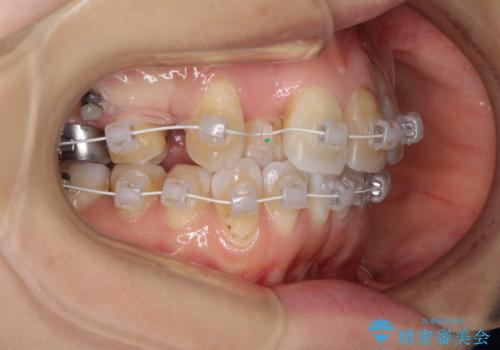

- 審美装置

- 1年7ヶ月

- 10-30回

右上4番目の歯を抜歯し、上顎裏側に補助装置を装着して左の歯列全体を後方に移動させながら、正中を合わせるようにして行くこととしました。